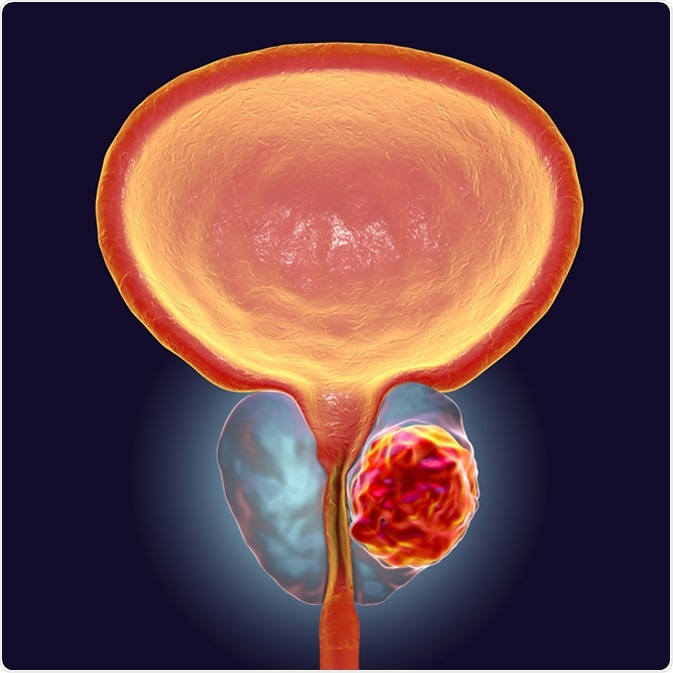

photos of prostate cancer

Prostate Cancer Illustration Stock Illustration – Illustration of …